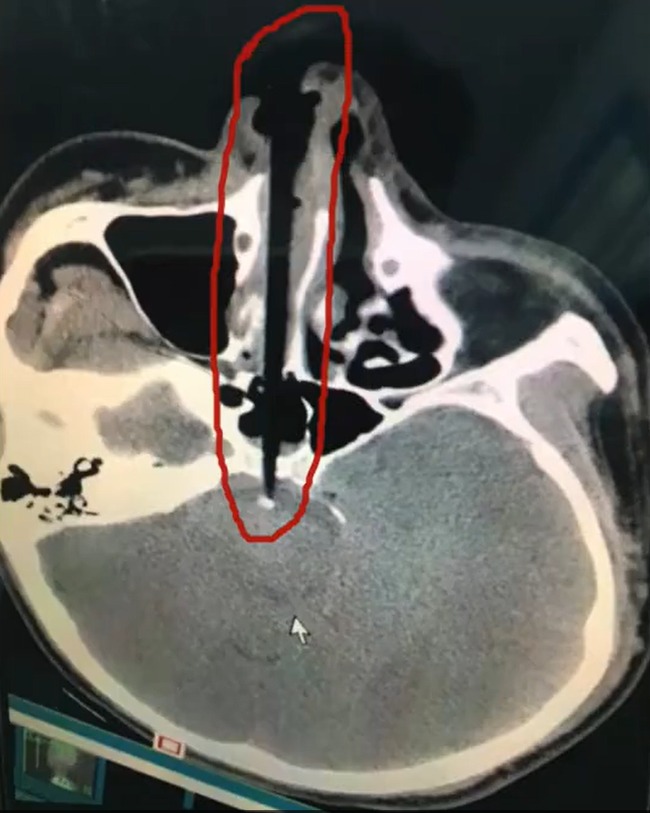

Người đàn ông đã nhận cái kết đắng lòng khi cố ngoáy mũi bằng đũa. Nhiều người thường có thói quen dùng ngón tay để ngoáy mũi, nhưng trường hợp người đàn ông ở TQ lấy đũa ngoáy đã phải trả giá thảm khốc cho hành động của mình.

Theo trang Shanghaiist, một người đàn ông sống ở Hồ Nam, Trung Quốc cảm thấy ngứa ngáy trong lỗ mũi sau khi ăn tối với gia đình. Ngay khi mọi người đứng dậy rời khỏi bàn, không thể chịu đựng được cơn ngứa, anh ta đã với lấy chiếc đũa và làm điều không tưởng: Nhét cây đũa và lỗ mũi và bắt đầu ngoáy mũi không ngừng.

Nhưng điều tồi tệ nhất không phải là chiếc đũa đó vừa để ăn cơm mà lại dùng để ngoáy mũi. Khi anh ta đứng dậy, bỗng bị vấp ngã và mặt cắm xuống đất. Như mọi người có thể tưởng tượng, chiếc đũa 20cm đã cắm thẳng vào hốc mũi. Khi mọi người nghe thấy tiếng kêu thất thanh và quay trở lại phòng ăn, ai nấy đều hãi hùng trước cảnh tượng trước mắt.

Ngay lập tức, anh ta được đưa đến bệnh viện gần nhất, các bác sĩ tiến hành phẫu thuật cấp cứu vì sợ rằng bất kỳ chuyển động nhỏ nào cũng có thể khiến chiếc đũa đẩy sâu vào bên trong hộp sọ.

May mắn là ca phẫu thuật thành công, người đàn ông này hiện đang phục hồi tích cực và sớm ra viện.